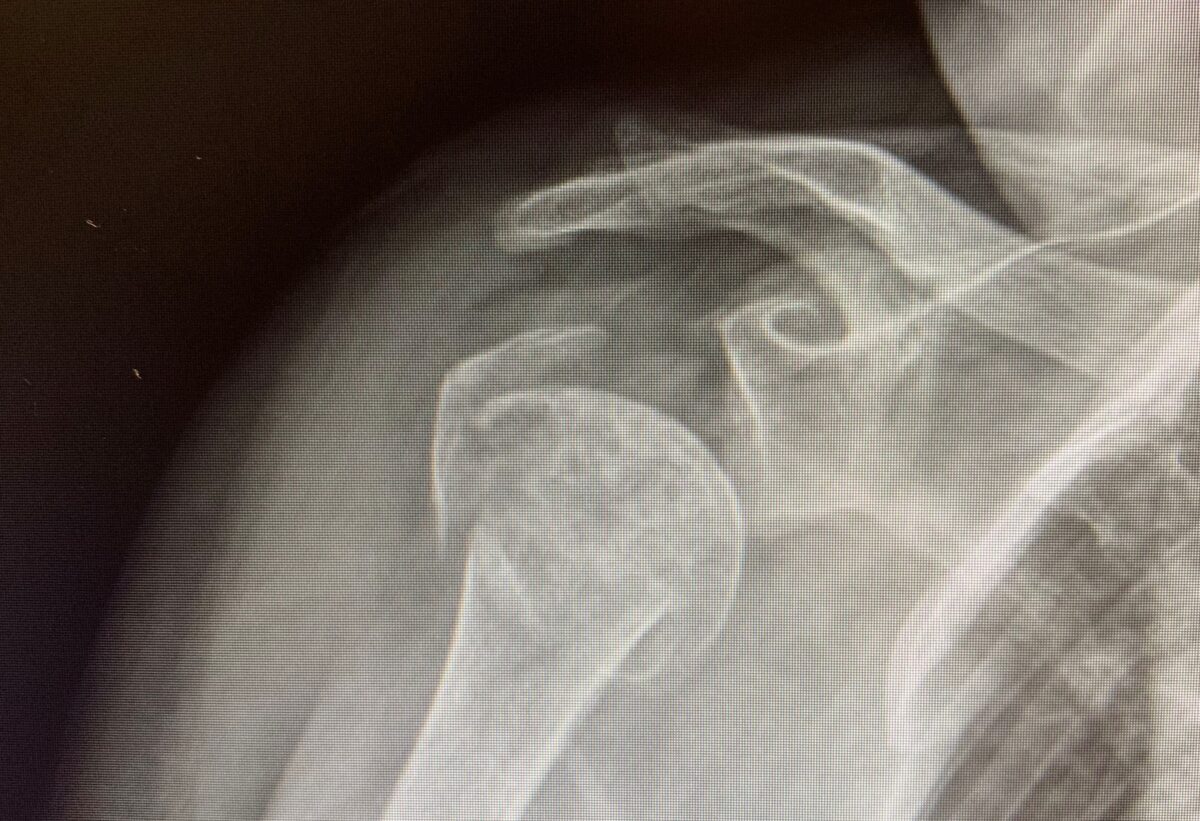

Fractured shoulder, Xray Stock Image F037/5544 Science Photo Library Shoulder Fracture Not Healing How long will it take to heal? We’ve prepared this overview to help you navigate through all stages of. Whatever your course of treatment, your doctor will likely recommend exercises during your recovery. Most fractures heal without any problems in six to twelve weeks. Many heal with rest and ice, but some need surgery. A shoulder fracture is a broken. Shoulder Fracture Not Healing.